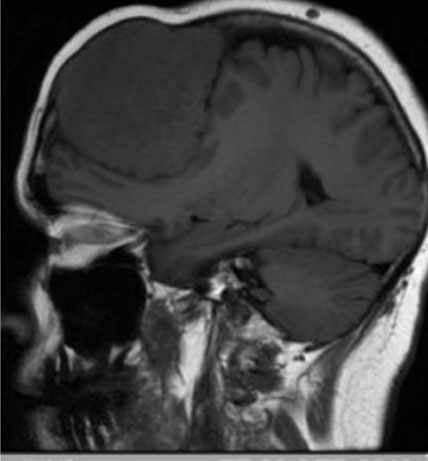

In addition to requiring oxygen, she reported right eye pain, photophobia, and nausea. The patient could only count fingers and recognize faces with the right eye. Computed tomography scan confirmed the presence of hyperdense, almost curvilinear, thickening seen postero-laterally in the right globe suggestive of retinal detachment. An ophthalmic examination revealed a large metastasis in right infero-temporal choroid with associated retinal detachment and no retinal tear (Figure 1). The contra-lateral left choroid was normal and remained so. Biopsy of a left breast mass during presentation with metastatic disease showed grade 3 breast carcinoma of no special type with Allred score ER 8, PgR 0, and HER-2 3+. She was commenced on chemotherapy and dual anti-Her-2 therapy with marked regression of the retinal lesion and improvement in her symptoms. The regimen given was 12 cycles of weekly paclitaxel 80 mg/m2 with Pertuzumab 840 mg intravenous (IV) and Trastuzumab 600 mg subcutaneously. Pertuzumab was discontinued after the first dose because of severe side effects, including gastro-intestinal upset. In total, she had 16 cycles of 3-weekly trastuzumab. Systemic treatment was eventually stopped because of breathlessness and decreasing fitness.

Figure 1: Before systemic dual-anti-HER-2-therapy and chemotherapy: Image of the right fundus showing a large metastatic lesion located temporally and involving the macula. There is associated exudative inferior retinal detachment. Images were captured using the Optos widefield, Monaco system.